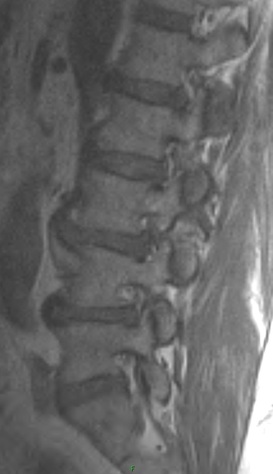

1. Aside from disc changes and spondylosis, what additional finding is present.

2. What are the types of spondylolisthesis? Pertaining to the anterolisthesis, which type does the patient have?

3. What is the appropriate way to asses stability?

4. What are treatment options for spondylolisthesis?